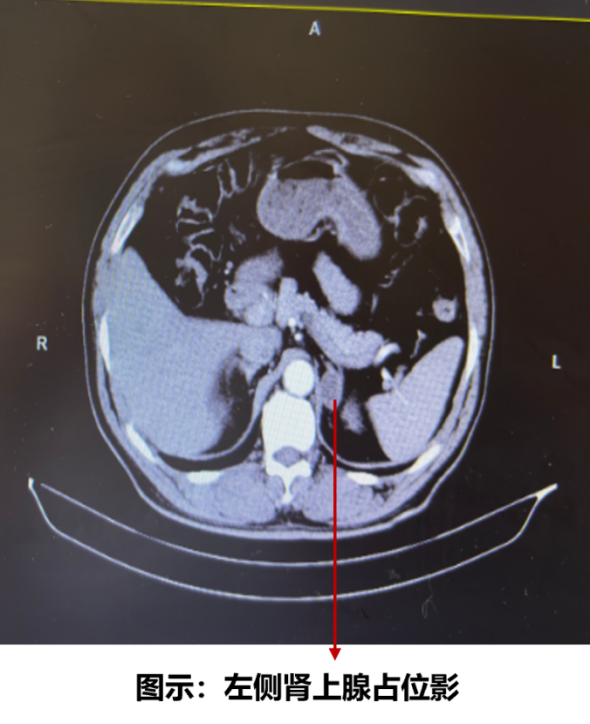

在评估难治性高血压时,常规进行了肾上腺影像学检查(CT),发现左侧肾上腺一约22*17 mm的低密度占位,影像学提示腺瘤可能性大(图2)。实验室检查报异常醛固酮(卧位),246.96 nmol/l,高于正常值范围(10~160nmol/l)。结合患者存在高血压、低血钾倾向,初步诊断原发性醛固酮增多症(Primary Aldosteronism,简称原醛症)。进一步通过“生理盐水试验”进行确诊,卧位醛固酮水平在试验前后均显著高于正常值(试验前246.96 nmol/l,试验后220.45 nmol/l),且不被生理盐水负荷所抑制,符合原醛症诊断。

图2. 肾上腺影像学CT检查

治疗与转归

后转入泌尿外科行左侧肾上腺腺瘤切除术。术后一个月后随访,其血压(130/80 mmHg)和血糖(空腹血糖:6.3 mmol/L;餐后血糖:6.6~9.0mmol/L)控制均得到显著改善,减少了降压和降糖药物的需求。